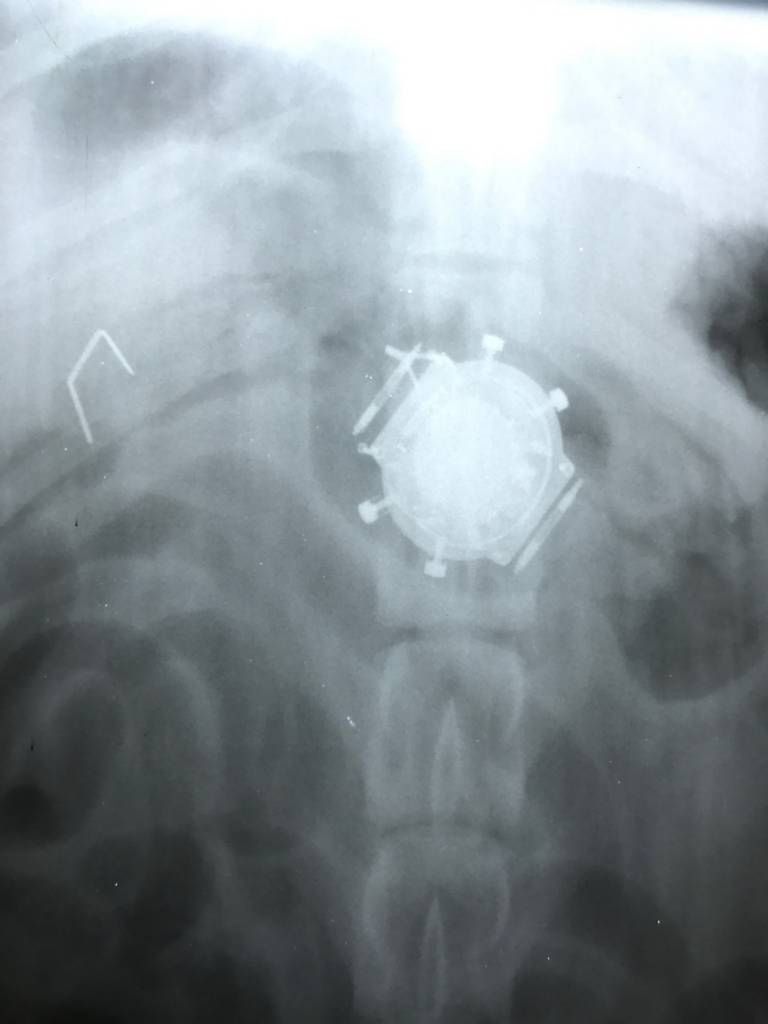

/ 11Dinozaury

Obraz

© Veterinary Practice News / Eileen V. Lindmeier, VMD, of Chalfont Veterinary Clinic LLC in Chalfont, Pa.

8-letni angielski buldog o imieniu Otis niedomagał i tracił na wadze, więc właściciel zabrał go do lecznicy. Po podaniu środka na przeczyszczenie z psa wyskoczyły dwa małe metalowe dinozaury. Prześwietlenie pokazało, że w Otisie zostały jeszcze dwa inne. W czasie operacji wydobyto obie figurki.